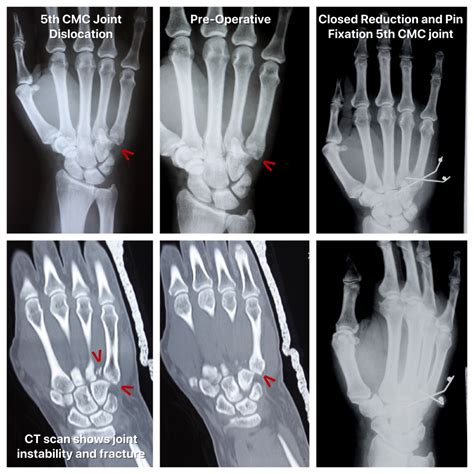

Diagnosing a displacement bone fracture typically involves a combination of physical examination and imaging tests. The diagnostic process usually includes:

• X-rays: These are the primary imaging tool used to visualize the bone and determine the extent of the fracture and displacement.

• CT scans: For more detailed images, especially in complex fractures, a CT scan may be ordered.

The treatment of a displacement bone fracture depends on the severity and location of the fracture. Common treatment options include:

• Reduction: This involves realigning the bone fragments, which can be done manually (closed reduction) or surgically (open reduction).

• Surgery: In severe cases, surgery may be required to realign the bone fragments and stabilize them with plates, screws, or rods.